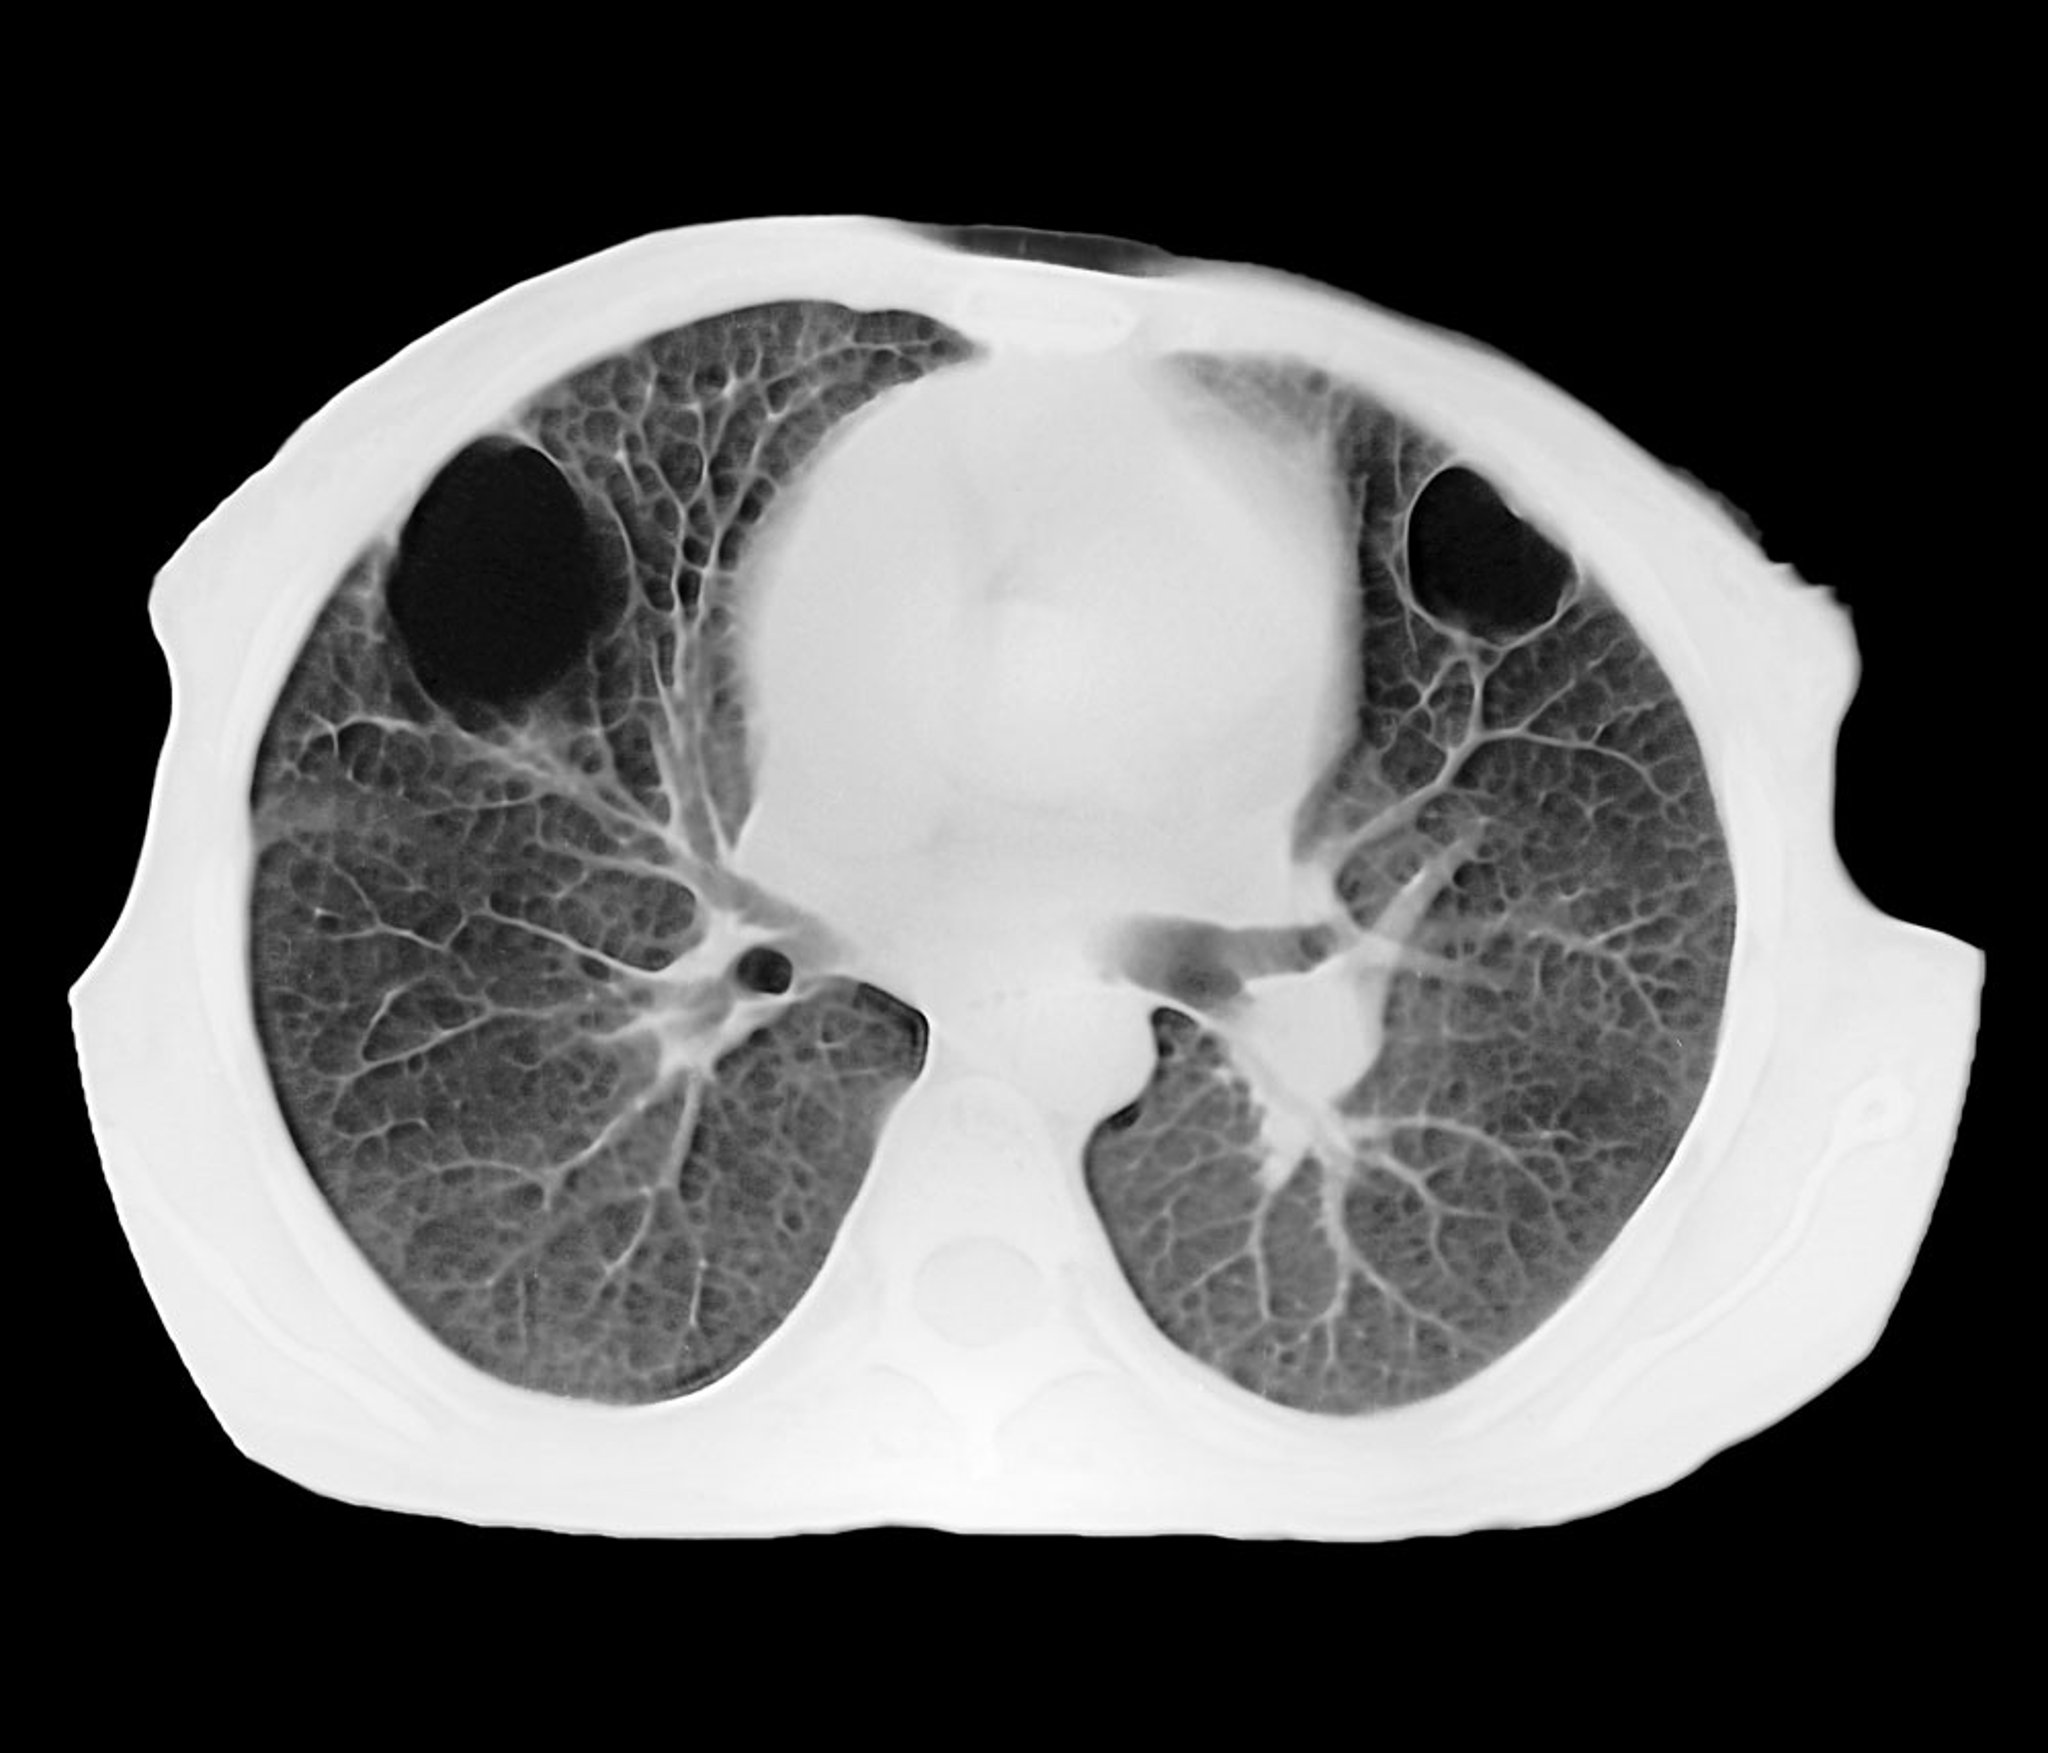

Abcès pulmonaire (TDM)

Cette tomodensitométrie axiale montre deux abcès pulmonaires parenchymateux bien circonscrits dans les lobes antérieurs droit et gauche. L’intérieur noir correspond à une accumulation de pus.

ZEPHYR/SCIENCE PHOTO LIBRARY